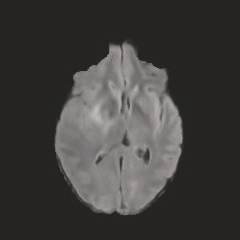

Multi-modal medical image completion has been extensively applied to alleviate the missing modality issue in a wealth of multi-modal diagnostic tasks. However, for most existing synthesis methods, their inferences of missing modalities can collapse into a deterministic mapping from the available ones, ignoring the uncertainties inherent in the cross-modal relationships. Here, we propose the Unified Multi-Modal Conditional Score-based Generative Model (UMM-CSGM) to take advantage of Score-based Generative Model (SGM) in modeling and stochastically sampling a target probability distribution, and further extend SGM to cross-modal conditional synthesis for various missing-modality configurations in a unified framework. Specifically, UMM-CSGM employs a novel multi-in multi-out Conditional Score Network (mm-CSN) to learn a comprehensive set of cross-modal conditional distributions via conditional diffusion and reverse generation in the complete modality space. In this way, the generation process can be accurately conditioned by all available information, and can fit all possible configurations of missing modalities in a single network. Experiments on BraTS19 dataset show that the UMM-CSGM can more reliably synthesize the heterogeneous enhancement and irregular area in tumor-induced lesions for any missing modalities.